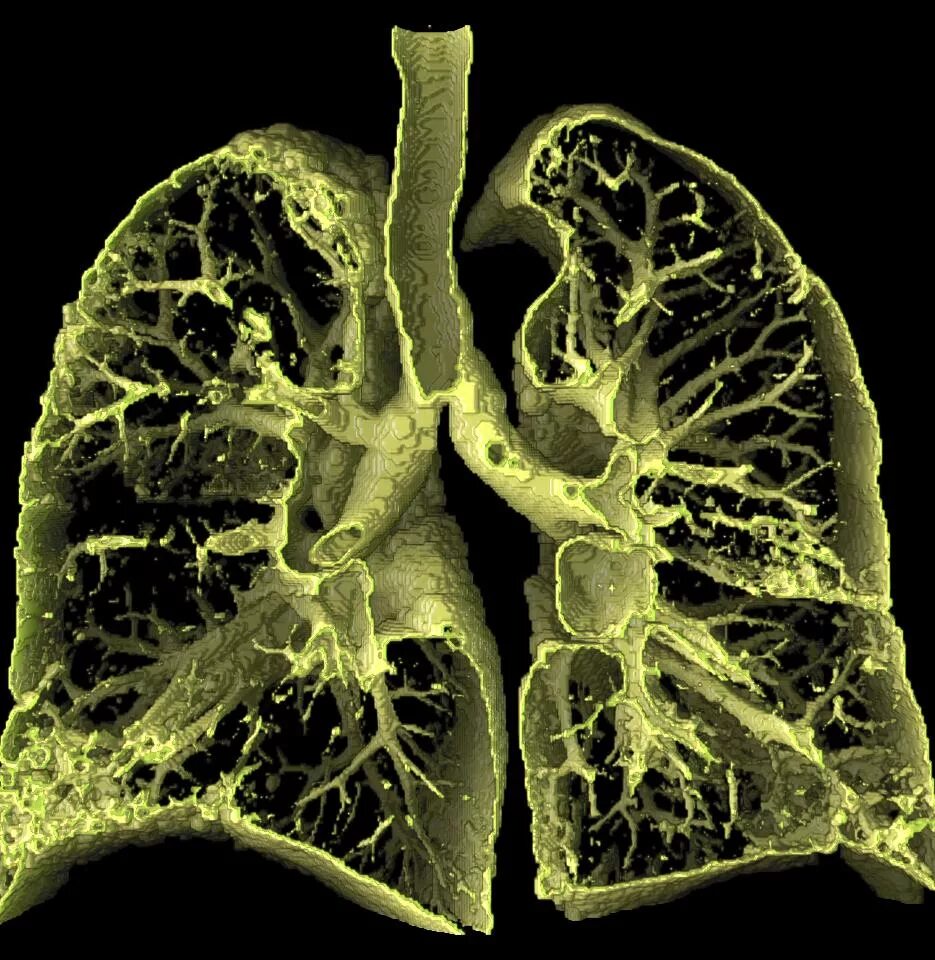

Дыхательная при пневмосклерозе